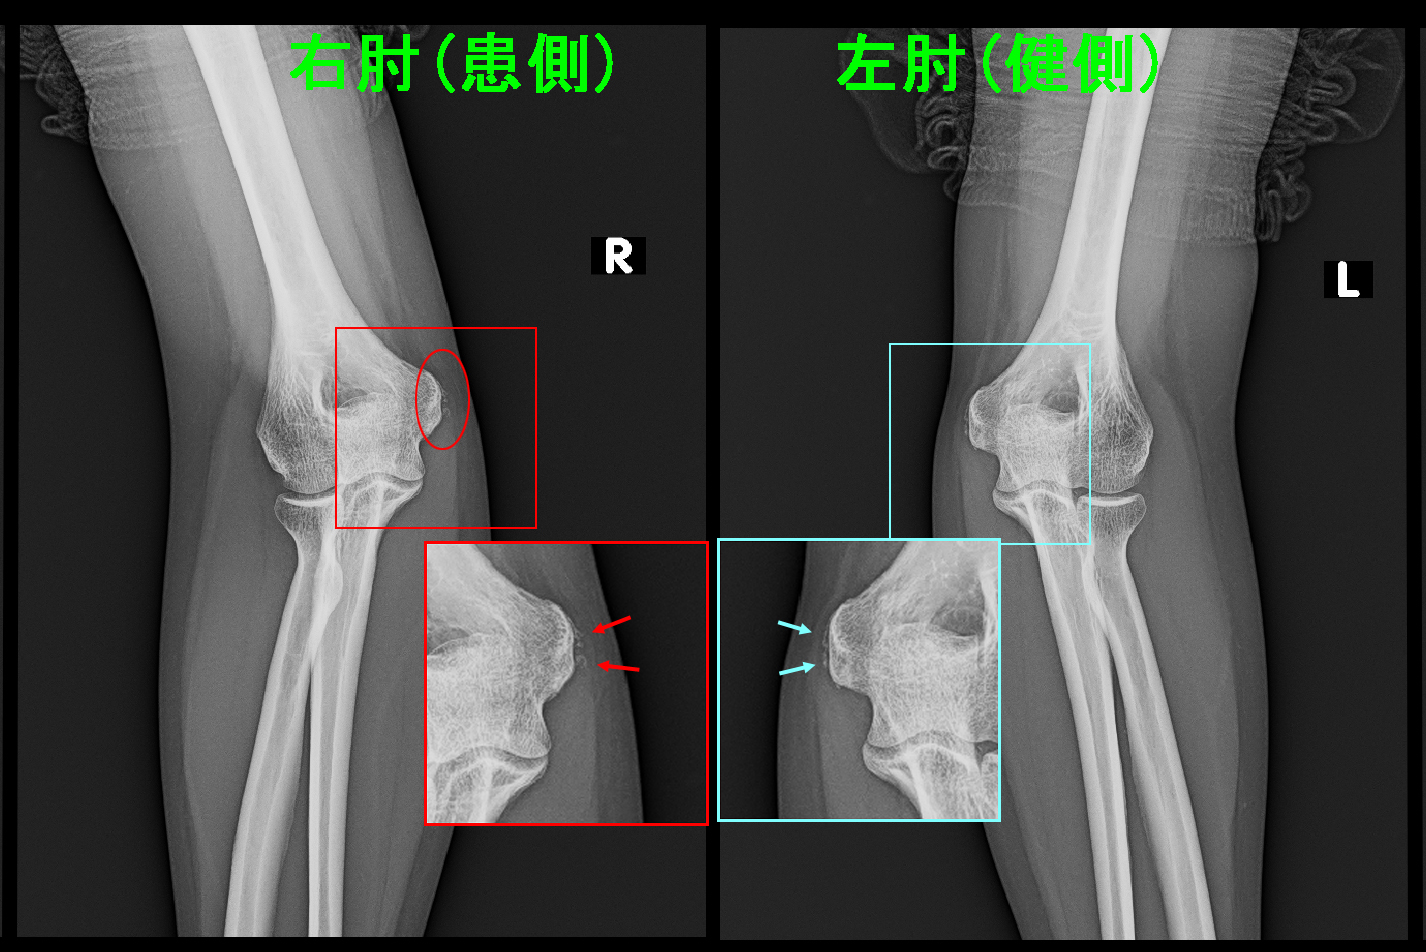

40才の男性です。レントゲンの赤丸領域に痛みを訴えた外側上顆炎の患者さんですが、令和5年の4月と9月に局注の治療を行い、治癒しています。同時期、手指の腱鞘炎の治療も行っていました。

40才男 局注治癒例.jpg令和7年10月に対側である左の外側上顆炎の痛みで受診されましたが、2年前の腱鞘炎の治療は覚えていたのですが、右の外側上顆炎の治療を行っていたことは忘れていました。

47才の女性でピアノ講師をしている方で、右内側上顆炎の患者さんです。赤丸領域の内側上顆にピアノを弾いた後にVAS7~8の痛みを感じて、令和5年10月に受診されました。レントゲンでは両内側上顆部に石灰沈着の所見を認め、左内側にも潜在的な炎症所見の可能性が示唆されています。